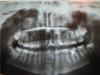

Katyalu Опубликовано 21 апреля, 2010 Поделиться Опубликовано 21 апреля, 2010 (изменено) Добрый день, уважаемые врачи!Не могли бы вы посмотреть мой панорамный снимок и сказать на сколько все кретично у меня во рту (если это конечно возможно). Дело в том, что когда я его делала врач сказала мне, что у меня в районе каждой 8 киста и возможен перелом челюсти И вообще может вы сможете мне сказать, что подлежит лечению, удалению и т.д.Заранее спасибо. Изменено 21 апреля, 2010 пользователем Katyalu Ссылка на комментарий

Scrabble Опубликовано 21 апреля, 2010 Поделиться Опубликовано 21 апреля, 2010 21 и 36-перелечивание, вкладки, коронки. 8-ые-недостаточно информации по орто, сходите к хирургу, прицельные снимки сделайте. Ссылка на комментарий

Katyalu Опубликовано 21 апреля, 2010 Автор Поделиться Опубликовано 21 апреля, 2010 (изменено) 21 и 36-перелечивание, вкладки, коронки. 8-ые-недостаточно информации по орто, сходите к хирургу, прицельные снимки сделайте.На самом деле это 11 и 46, снимок получился перевернутым косячокс мойПро 46 я так и думала, что его нужно переличивать, но не думала, что и в 11 каналы плохо запломбированы.... скажите, что с ним не так... Изменено 21 апреля, 2010 пользователем Katyalu Ссылка на комментарий

Scrabble Опубликовано 21 апреля, 2010 Поделиться Опубликовано 21 апреля, 2010 Качество обтурации КК 11 по орто трудно оценить, но раз имелась негерметичная реставрация-эндоревизия не повредит. Ссылка на комментарий